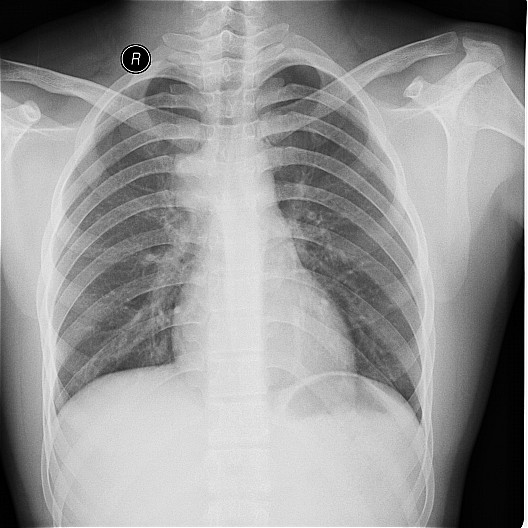

一钨矿工厂因有毒气体泄漏(据说是硝酸)造成十多名工人中毒,均出现不同程度的咳嗽,气逼,心跳加快等中毒症状.其中有几例患者胸片出现小点片状,结节状阴影.是此次中毒引起的肺部改变还是原来就患有矽肺病或其它病变.

肺水肿,及原来就患有矽肺病

原就有的矽肺,未见中毒性肺水肿

矽肺,部分胸片可见肺水肿。治疗复查